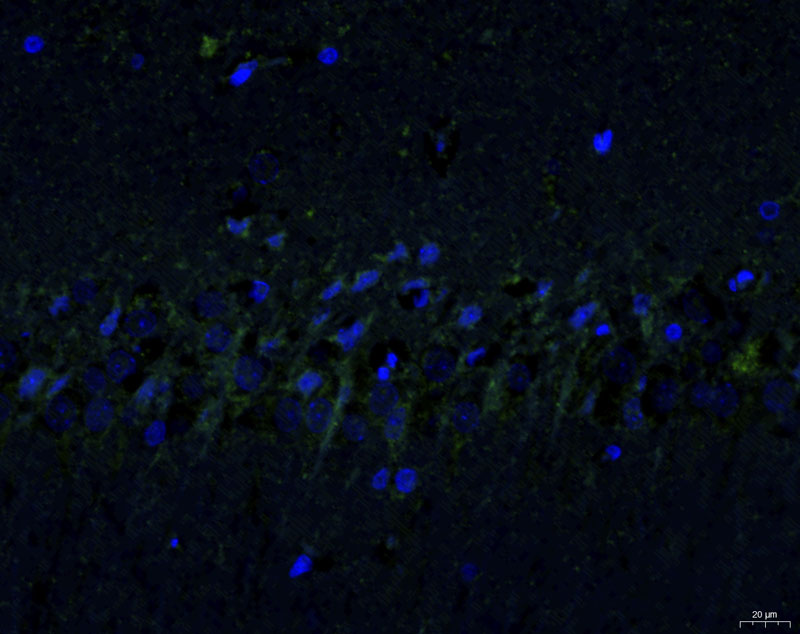

模型組1-1-40X-DAPI

模型組1-2-40X-G

模型組1-3-40X